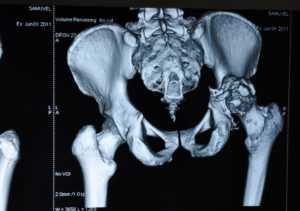

Снимок компьютерной томографии перелома таза в области вертлужной впадиныДля того чтобы быть полностью уверенным в диагнозе, врач также назначает пройти диагностирование на компьютерной томографии. Благодаря такому методу диагностирования можно точно обнаружить смещение или присутствие оскольчатого перелома. Для определения открытого перелома проводится ректальное и вагинальное обследование.

- трехпроекционная рентгенография таза и самого сустава;

- компьютерная томография.

Компьютерная томография таза

Данные исследования позволяют установить какой именно участок вертлужной впадины был разрушен, есть ли смещение костей. С целью оценить неврологическую составляющую для консультации приглашается невропатолог. На основе собранных данных врач формирует диагноз и определяет тип перелома.

Рис — Перелом дна вертлужной впадины со смещением. Снимки до и после операции

Ставят диагноз основываясь на симптомах, данных рентгенологического и КТ исследований. Рентген делают в нескольких проекциях, снимок в прямой проекции оказывается малоинформативным для установления характера полученных повреждений.

КТ проводят для постановки более точного, правильного диагноза. Она позволяет определить наличие или отсутствие смещения костных фрагментов. Ректальным и вагинальным методами исследования определяют характер перелома, он может быть открытым или закрытым.